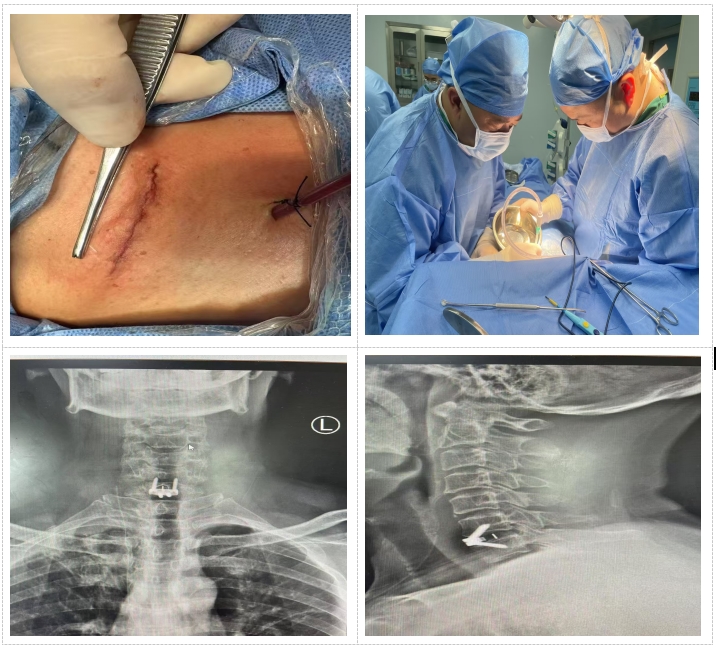

患者因"頭痛、雙上肢麻木伴下肢乏力1月"入院,此前長期保守治療效果不佳,癥狀持續(xù)加重并出現(xiàn)行走不穩(wěn)。經(jīng)多學科聯(lián)合會診,團隊決定采用國際先進的零切跡cage融合術。手術歷時2小時,出血量僅10ml,術后患者即刻感到頸部及肢體癥狀顯著緩解,術后三天即可下床活動,微創(chuàng)切口(3—4厘米)及快速康復效果獲家屬高度贊譽。

1.采用小型化、低切跡的融合器(cage),切口僅3—4厘米,術中對軟組織剝離少,有效降低血管、神經(jīng)損傷風險;